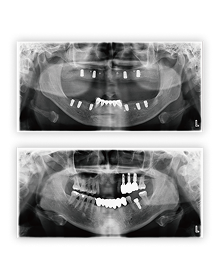

임상증례

티타늄 메쉬

Clinical Case